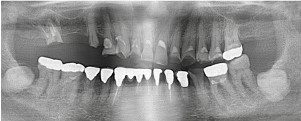

治療前のレントゲン

治療後のレントゲン

奥歯が欠損してから長期間放置していたため、残っている歯が著しく摩耗しており、かみ合わせが崩壊して新たに入れ歯を作ることも困難な状態でした。まず、関係する歯をすべて仮歯にしてから全体のかみ合わせの高さを上げ、咬合を再構成しました。上下前歯はジルコニアオールセラミックで仕上げました。奥歯は保険適用の金属冠、欠損している下の奥歯は金属床義歯を装着しました。